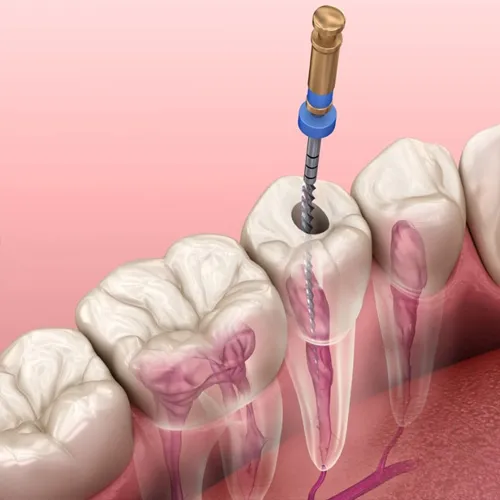

5. Instrumentarea canalelor

Cu ace manuale sau rotative din NiTi (nichel-titan), care oferă:

- flexibilitate mare

- precizie

- adaptare la canale curbe

6. Dezinfecția canalelor

Cu soluții moderne precum:

- hipoclorit de sodiu

- EDTA

- clorhexidină

- activare ultrasonică pentru eficiență superioară